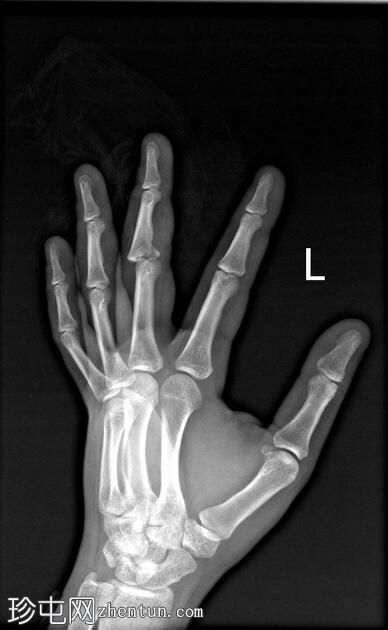

正位

可见第三指中节指骨基底部轻微移位骨折,延伸至近端指间关节(PIP关节),并伴有软组织肿胀。

第三指中节指骨基底部轻微移位骨折,延伸至近端指间关节(PIP关节)指骨,并伴有软组织肿胀。